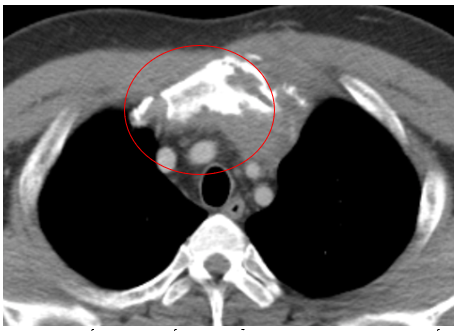

CASE LÂM SÀNG Điều trị bệnh nhân mắc đồng thời hai loại ung thư: Ung thư phổi và ung thư...

Case lâm sàng: Điều trị miễn dịch kết hợp thuốc kháng tăng sinh mạch cho bệnh nhân ung thư biểu mô tế bào gan tại trung tâm y học hạt nhân và ung bướu – BV Bạch Mai

Case lâm sàng: Điều trị miễn dịch kết hợp thuốc kháng tăng sinh mạch cho bệnh nhân ung thư biểu...